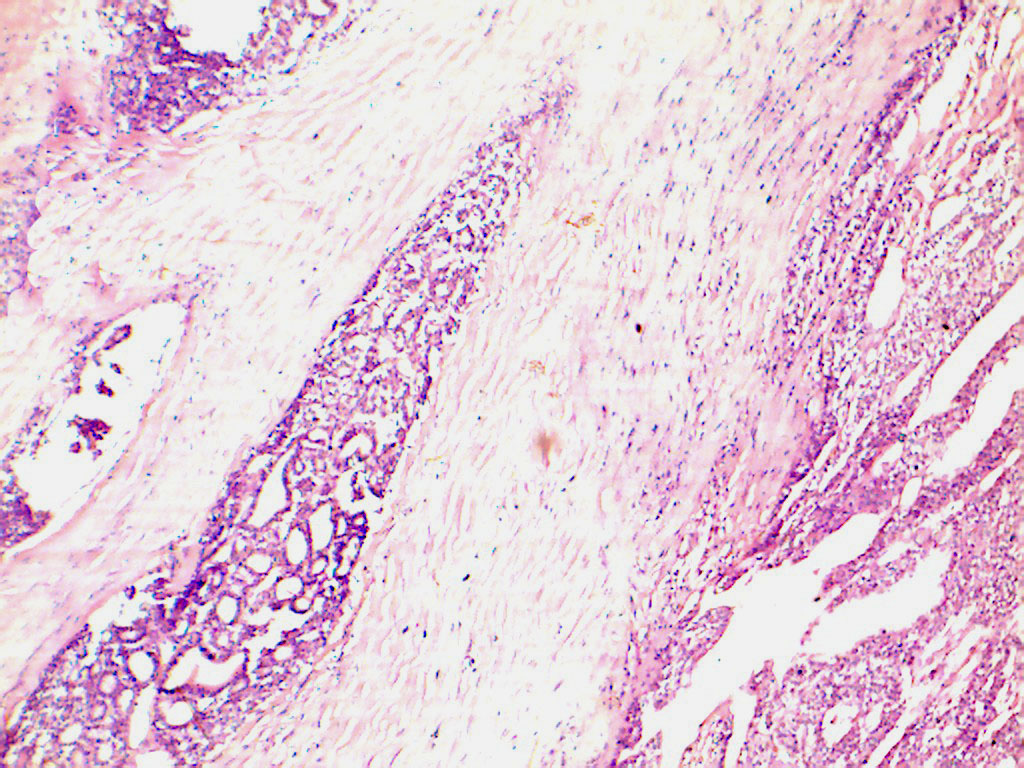

Thyroidectomy was performed and multiple sections were taken from the sent specimen from the representative areas. The sections revealed an encapsulated tumour with the cells arranged mainly in follicles showing mild to moderate pleomorphism. Capsular and vascular invasion was seen at a few places [Table/Fig-3]. A final diagnosis of FCT with metastases of same to the pelvic region was given. The patient was admitted in the oncology unit. Treatment modality was planned as radiotherapy+ chemotherapy with probable surgery on a later date. Patient refused CT scan and scintiography owing to economic reasons. So it was not possible to predict whether the metastasis was an isolated event or more bony metastasis were also present. The patient was initially started with methimazole to first stabilize the hormone levels and then to initiate the combined therapy. The patient however; was lost to follow-up after a month and no further treatment was possible.

Histopathological section showing capsular invasion by the tumour cells. (H & E 400 X)